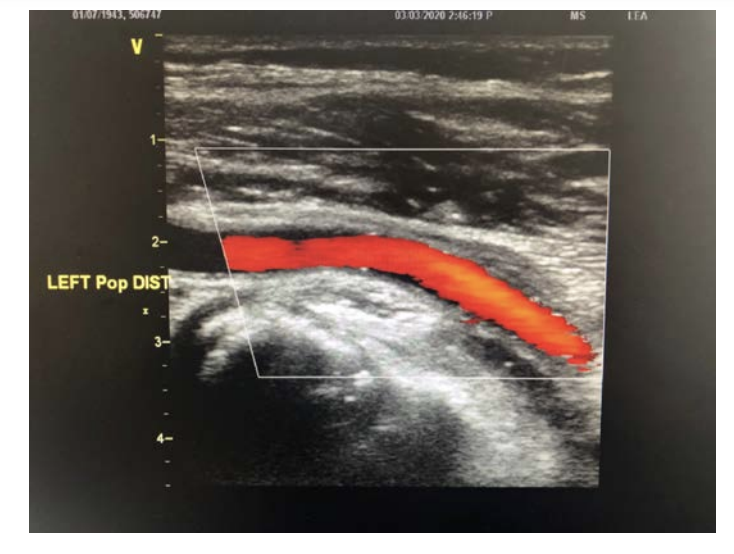

Nine months later, a follow-up arterial duplex ultrasound demonstrated the presence of normal triphasic flow in the proximal and distal popliteal artery with preservation of the lumen (Figure 6). The patient remains active and free of symptoms.